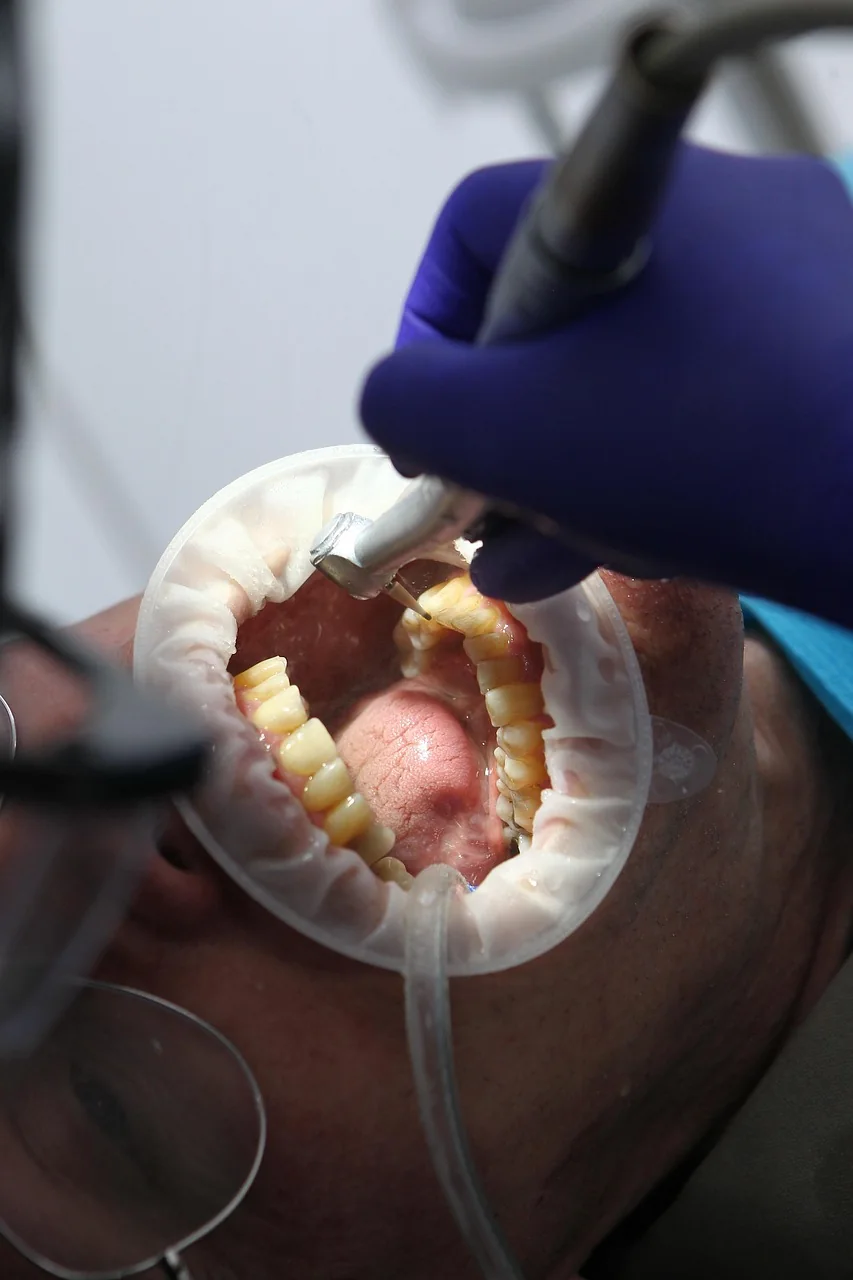

Endodoncja wymaga spokoju, precyzji i zdolności przewidywania. Nie każdy ząb udaje się uratować, ale dzięki odpowiednim protokołom i doświadczeniu klinicznemu podejmuję decyzje, które są najkorzystniejsze dla Pacjenta.

W Endocommunity pokazuję realny warsztat: analizę trudnych przypadków, ocenę rokowania i szczegóły, które mogą zepsuć wynik leczenia kanałowego.

Rozpisane krok po kroku: na co zwrócić uwagę w diagnostyce radiologicznej i jakie ma ona odzwierciedlenie w rzeczywistości pod mikroskopem.